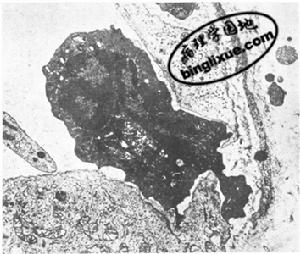

乾酪樣壞死:結核結節中心的乾酪樣壞死,內含壞死的組織細胞、白細胞和結核桿菌,組織壞死徹底,鏡下僅見一些無定形的顆粒狀物質,這可能是細胞介導免疫反應的結果。

上皮樣細胞(epithelioid cell):上皮樣細胞胞體較大,胞漿豐富,細胞之間境界不清,多分布於乾酪樣壞死灶周圍,其胞核呈圓形或卵圓形,染色質少,呈空泡狀,可見核仁,因這種細胞形態與上皮細胞類似,故有上皮樣細胞之稱。上皮樣細胞是因巨噬細胞吞噬一些不能被消化的細菌或受到其它抗原物質的長期刺激轉化而來的。

多核巨細胞(multinucleated giant cell):在上皮樣細胞之間散在多核巨細胞,結核結節中多核巨細胞又稱為朗漢斯巨細胞(Langhans giant cell)。胞體很大,直徑達40~50μm。細胞核形態與上皮樣細胞相似,數目可達幾十個,甚至百餘個,排列在細胞周邊部呈馬蹄形或環形,胞漿豐富。Langhans巨細胞一般由上皮樣細胞融合而成。

多核巨細胞還常見於不易被消化的較大異物(如手術縫線、石棉纖維等)和代謝產物(如痛風的尿酸鹽結晶)周圍。多個巨噬細胞圍繞在刺激物周圍並互相融合,形成異物多核巨細胞(foreign body multinucleated giant cell),多見於異物刺激引起的慢性肉芽腫性炎。